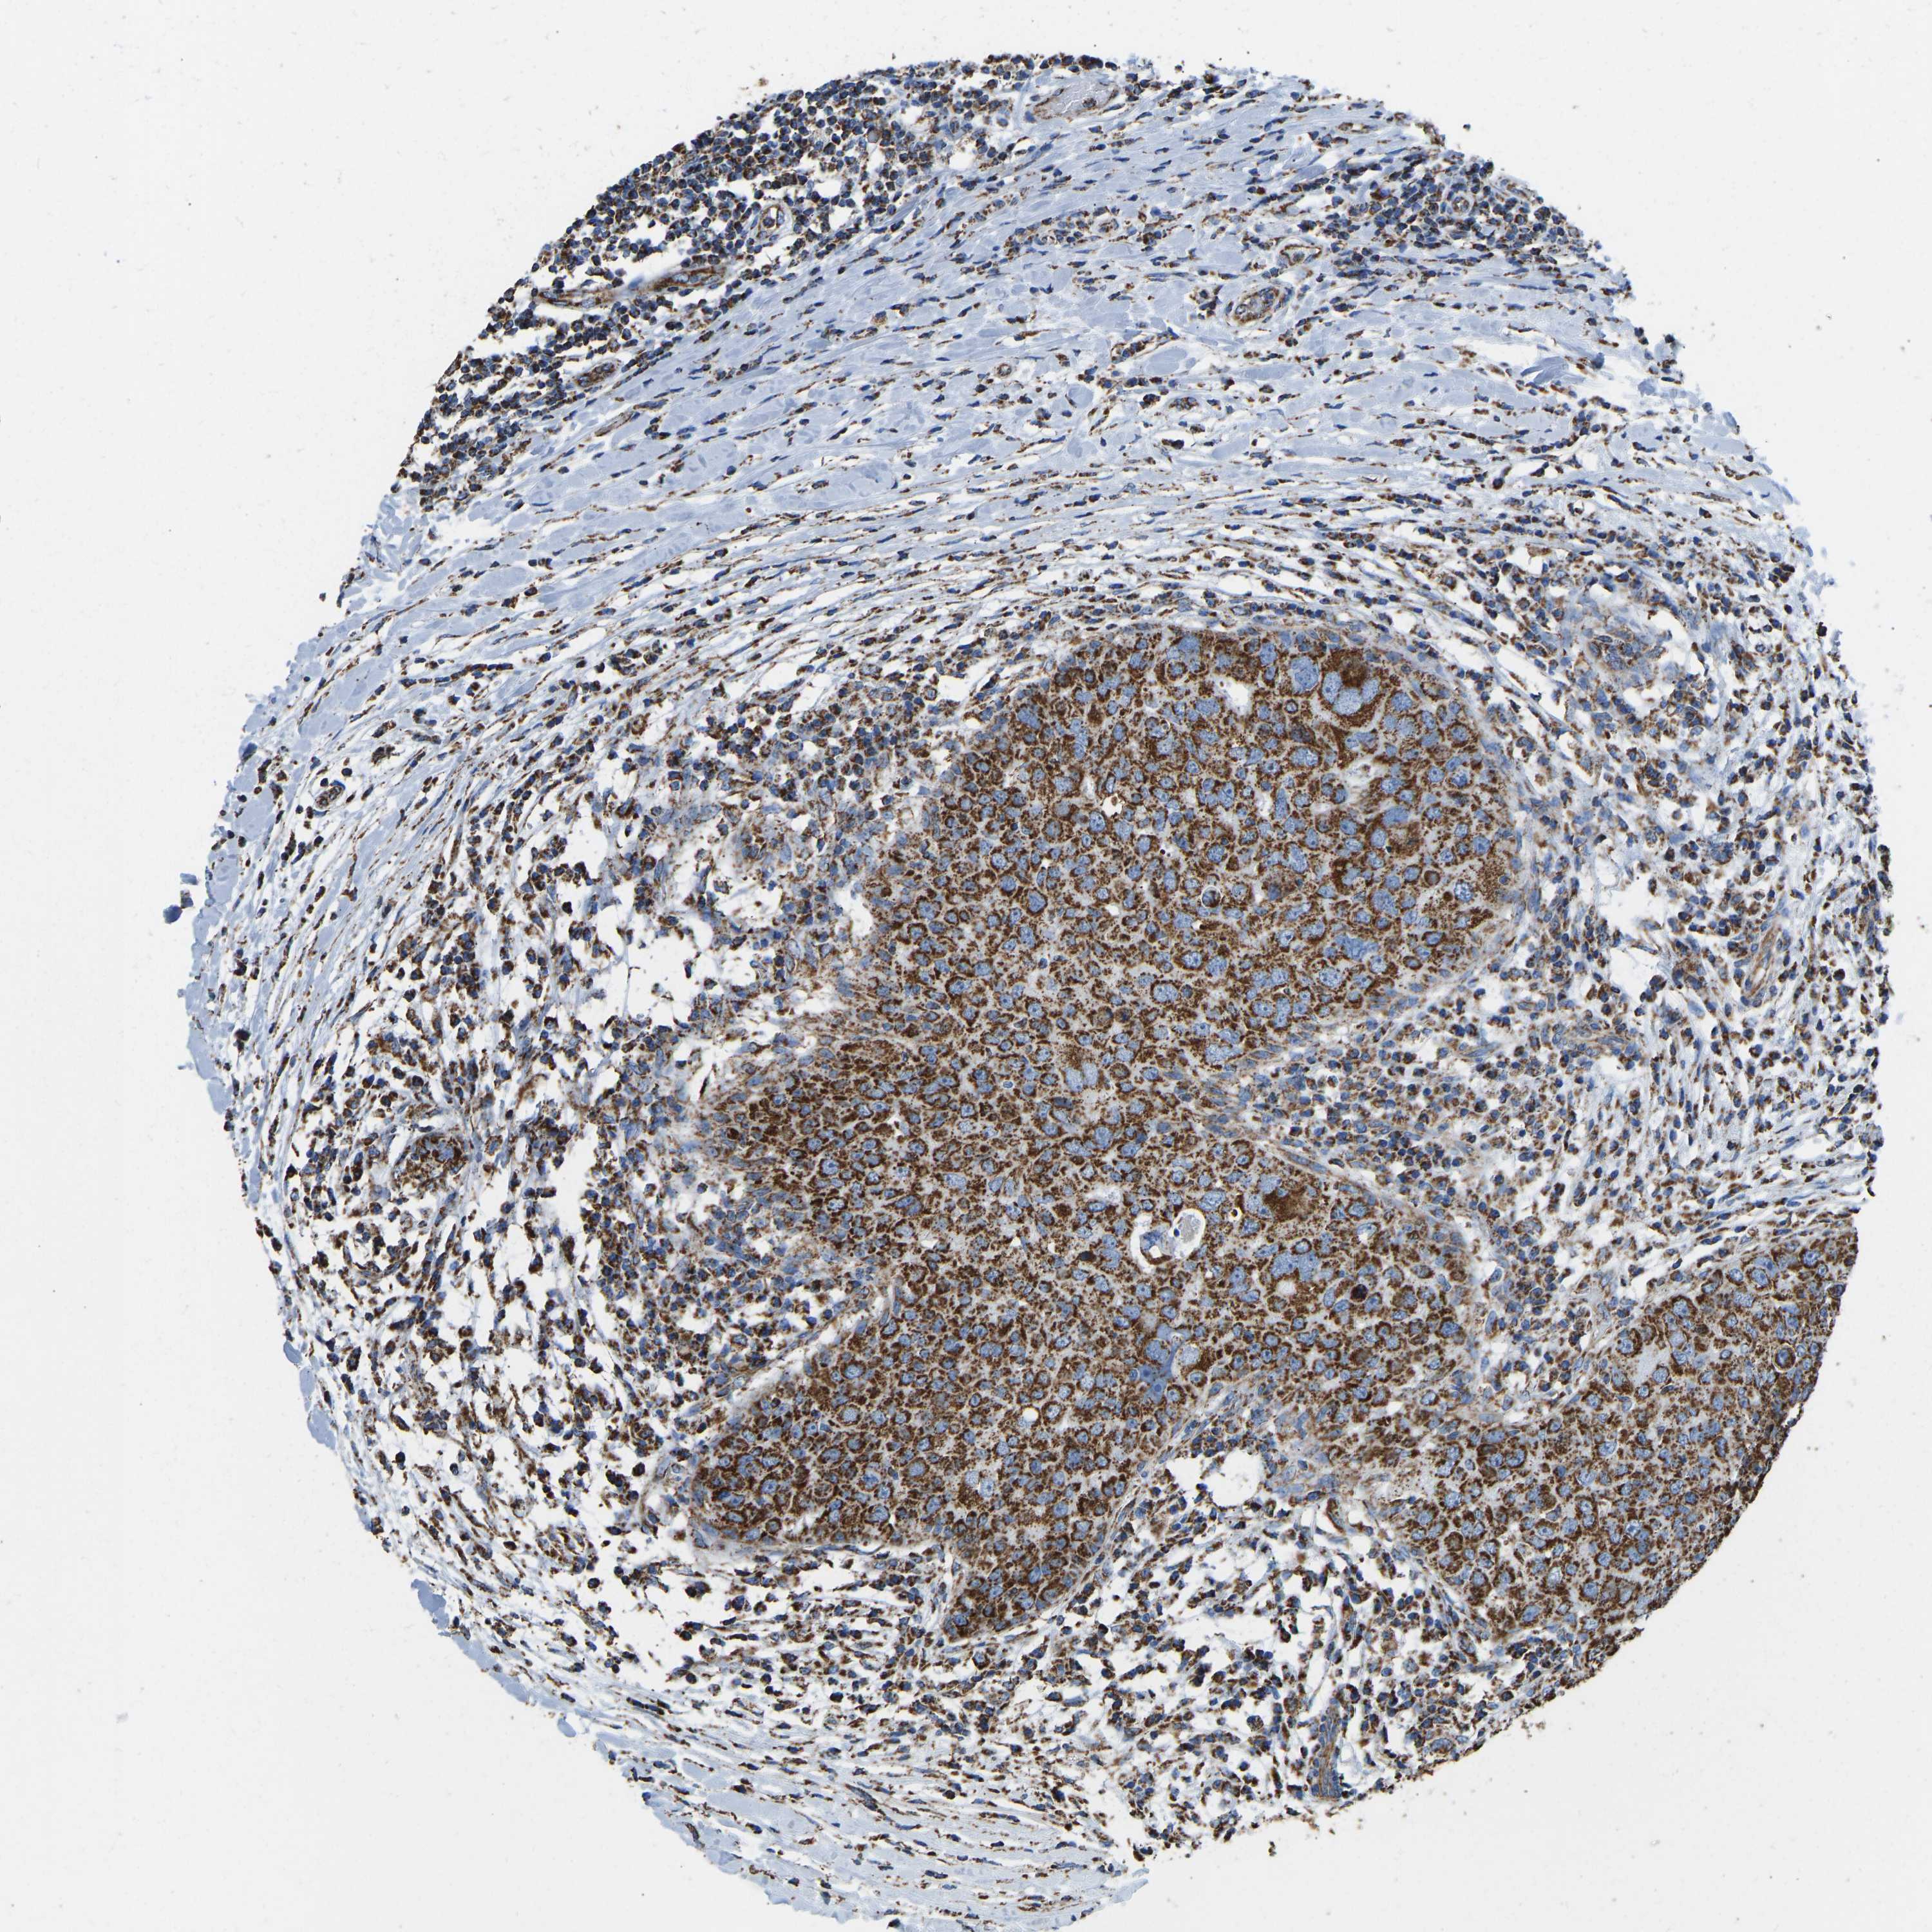

BRCA TCGA BRCA VALIDATION PROTEIN EXPRESSION

ANTIBODIES

AND

VALIDATION